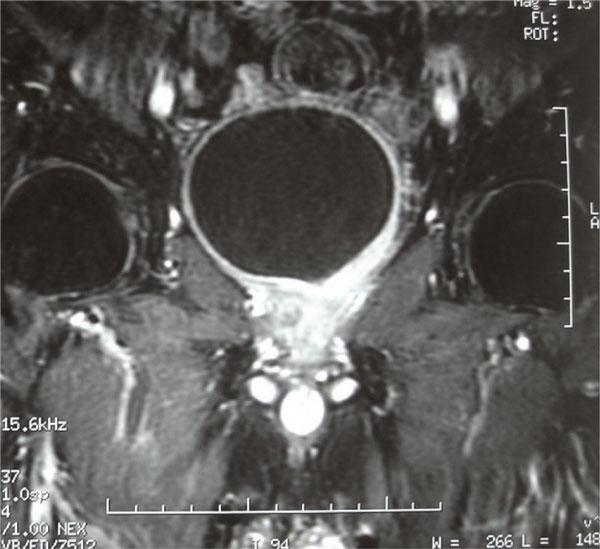

An 84-year-old man was admitted to our hospital having signs and symptoms suggestive of prostatic disease for 3 years. Histological and immunocytochemical studies of trans-urethral biopsy of the prostate showed diffuse large B-cell lymphoma. Radiological assessment of disease confirmed the diagnosis of early stage lymphoma of the prostate. The patient was managed by 6 of rituximab 375 mg/m2 on day 1, cyclophosphamide 750 mg/m2 on day 1, doxorubicin 50 mg/m2 on day 1, vincristine 1.4 mg/m2 on day 1, and prednisone 50 mg/m2 on days 1 to 5 with complete clinical and radiological response. He remained disease free, until now, 30 months after the end of chemotherapy.

一名84岁男性因有前列腺疾病的体征和症状3年而入住我院。经尿道前列腺活检的组织学和免疫细胞化学研究显示为弥漫性大B细胞淋巴瘤。疾病的影像学评估证实了早期前列腺淋巴瘤的诊断。患者接受了六个周期的治疗,第1天使用利妥昔单抗375mg/m²,第1天使用环磷酰胺750mg/m²,第1天使用多柔比星50mg/m²,第1天使用长春新碱1.4mg/m²,第1至5天使用泼尼松50mg/m²,临床和影像学均完全缓解。化疗结束30个月后,截至目前他仍无疾病复发。